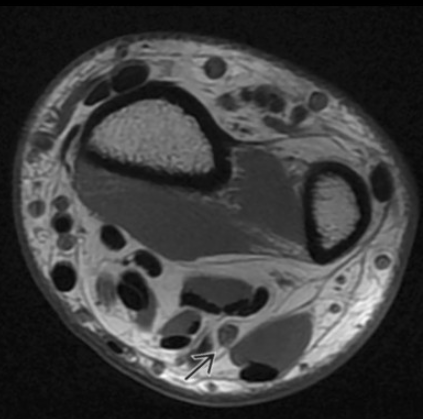

Lipomatosis of Nerve

• Basically fatty infiltration of the nerve

• If occurs in median nerve will result in thenar atrophy similar to carpal tunnel syndrome

• Has the coaxial cable appearance

• If you see fat in the lesion it excludes a neurofibroma or schwannoma which are other items in the ddx